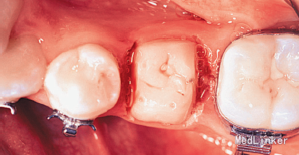

2年正畸治疗结束后,乳磨牙仍在。一年以后,患者18岁成年,拔除乳磨牙,植入植体,半年后套冠,效果很好,患者满意。有些先天缺失第二前磨牙的患者,若第二乳磨牙比较健康,可以减径后树脂修复参与正畸治疗,这样有保存骨量,维持牙弓间隙,保持与对合牙功能接触以免对合牙伸长的作用。骨量的保存利于植体的植入。